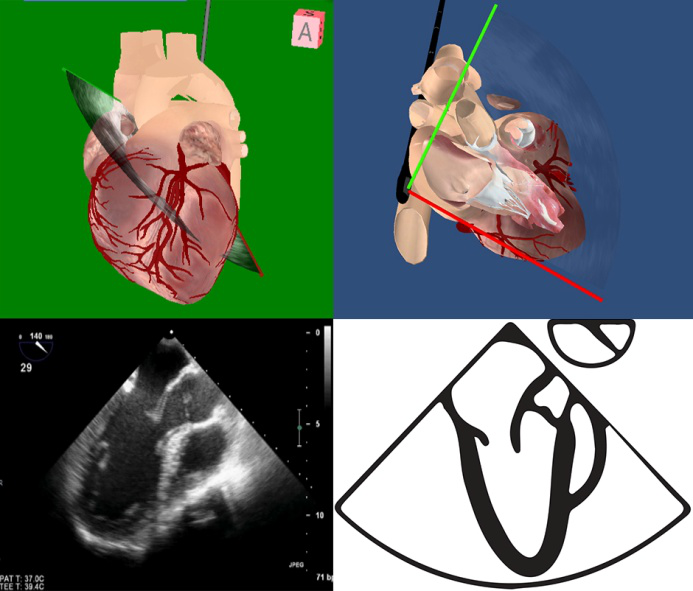

TEE切面可用来评估二尖瓣系统的每一部分,检查时将探头送至食管中段,操纵探头调整成像的角度使声平面对准二尖瓣环中心,探头晶片置于0~10度食管中段4腔心切面后开始旋转声平面,依次获得食管中段二尖瓣交界切面、食管中段左心室2腔切面、食管中段左心室长轴切面,在各个标准切面上可以观察不同小叶的功能状态,各个小叶与标准切面的对应关系如下图所示。

图10 TEE评价二尖瓣形态和功能的基本切面(标注二尖瓣分区)

TEE切面与二尖瓣分区的对应关系可用于二尖瓣脱垂部位的判断,但要注意的是:一定要将2D或3D图像与二尖瓣模型对应起来,不理解切面和模型之间的空间关系,直接用文献上的分区对应实际的超声图像会导致定位不准和交流障碍(图11,12,13,14);另外,经胃底基底段短轴切面对诊断瓣叶裂和穿孔很有帮助,彩色多普勒可以提供有关反流束起源的信息(图14)。

图13食管中段左室长轴切面显示二尖瓣后叶P2区腱索断裂并脱垂